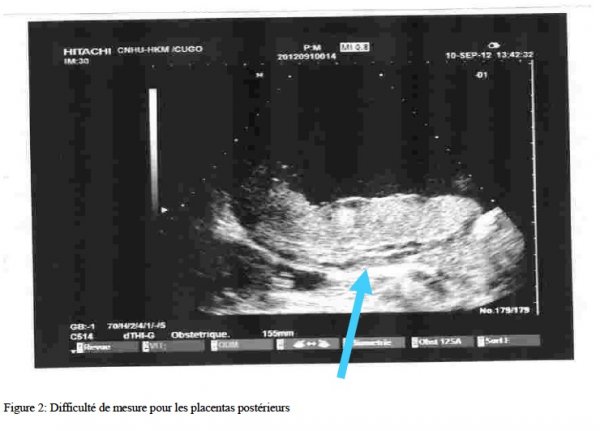

L’imagerie à résonnance magnétique (IRM) est un examen utile, en complément de l’échographie, permettant d’améliorer la performance diagnostique de cette dernière. Elle trouve pleinement sa place en cas de localisation placentaire postérieure, dans les formes percreta pour déterminer le degré d’invasion placentaire et dans le cadre de surveillance d’un placenta accreta laissé en place en cas de traitement conservateur.

Il a été diagnostiqué un cas de placenta accreta. Il s’agissait de Mme Z.K. âgée de 42 ans, adressée au service d’échographie de la clinique universitaire de gynécologie obstétrique (CUGO) du CNHU-HKM de Cotonou pour une suspicion de placenta praevia. La gestante était 7ème geste, 2ème pare, aux antécédents d’une césarienne et de 4 fausses couches spontanées dont deux suivies de curetage. Le suivi de la grossesse en cause, a débuté après 07 semaines d’aménorrhées (SA). L’échographie au 1er trimestre, réalisée à 12 SA était normale. L’échographie morphologique au 2ème trimestre réalisée à 23SA et 5 jours à montré un placenta postérieur bas inséré type 2. L’échographie réalisée à 33SA a conclu à une insertion placentaire antérieure fundique avec un oligoamnios modéré . Compte tenu de la confusion sur la localisation placentaire, une échographie de contrôle à 36 SA a été réalisée, montrant un placenta postéro-latérale droit, recouvrant le col avec un liseré hypoéchogène entre le placenta et l’utérus, mesurant 5 mm sur une étendue mal définie (Fig. 1, 2), la vascularisation au doppler de la zone suspecte est sans signe vasculaire anormale. Un placenta accreta a été suspecté. Devant un score de Manning défaillant par un oligoamnios modéré, une hospitalisation a été préconisée pour une surveillance foeto-maternelle.

L’individualisation des groupes à haut risque pour le placenta accreta est primordiale. Elle va nous orienter dans les démarches diagnostiques. Un interrogatoire minutieux, détaillant l’âge et les antécédents gynéco-obstétricaux, permet de suspecter et de bien évaluer les risques d’avoir un placenta accreta chez une gestante. Dès la suspicion de cette pathologie, une échographie de référence couplée au Doppler doit être réalisée systématiquement. Les critères échographiques recherchés sont les lacunes intraplacentaires, les vaisseaux traversant le myomètre et la disparition du liseré hypoéchogène entre le placenta et le myomètre. L’IRM, si elle existe, ne sera réalisée qu’au cours du bilan d’imagerie complémentaire dans les suspicions d’insertion accreta de découverte échographique ou chez des patientes a risques pour lesquelles l’échographie n’est pas ou peu contributive (localisation placentaire postérieure, morphotype maternel). Des procédures de dépistage prénatal du placenta accreta doivent être organisées car les risques foeto-maternels sont lourds.